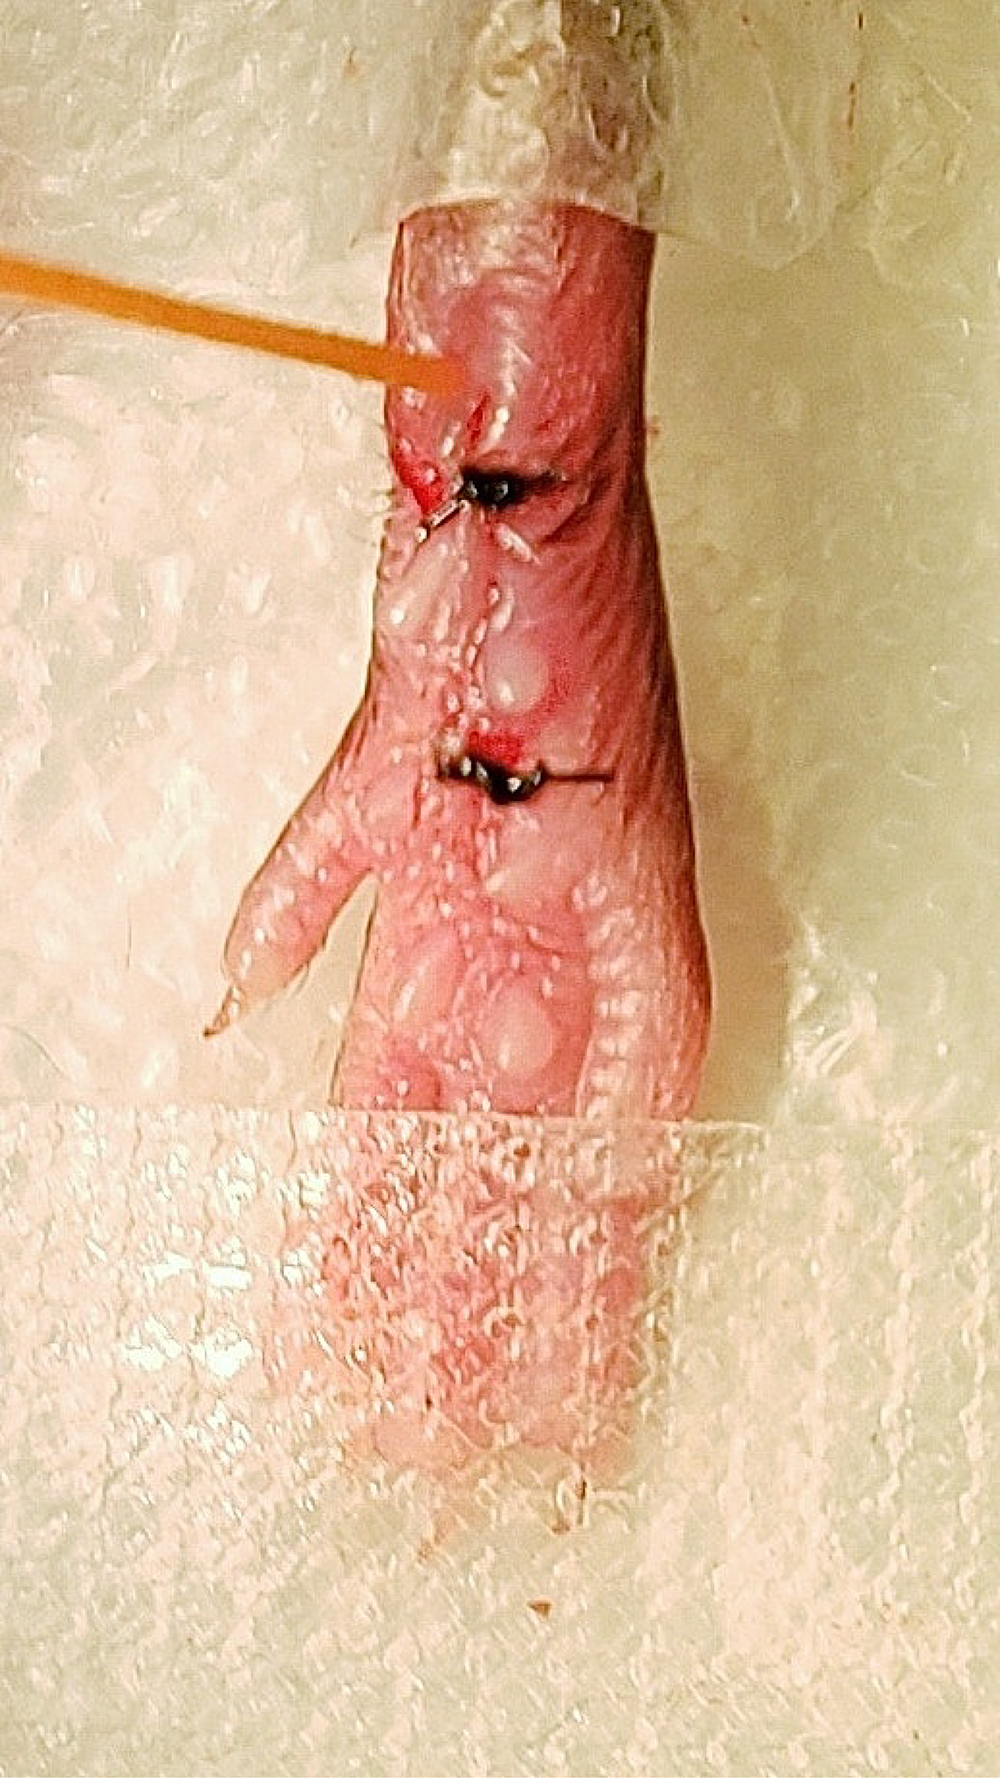

- For consistent behavioral results, apply mechanical and heat stimuli to the medial-posterior aspect of the plantar hindpaw (Figure 9). This area is the least sensitive at baseline because the heel is weight bearing whereas other areas near the pads are more sensitive and variable in withdrawal threshold. Therefore, using the heel area that provides a consistently high baseline withdrawal threshold allows for the best detection of change due to incision (Brennan et al., 1996). Mice were acclimated for 1 h in Plexiglass chambers placed on either a mesh platform (mechanical threshold) or glass platform (heat threshold). Calibrated von Frey monofilaments (0.09 to 19.6 mN) were applied to the plantar hindpaw and the withdrawal threshold for each animal was calculated using the up-down method (Dixon, 1980; Chaplan et al., 1994). The Hargreaves assay was used to measure heat sensitivity as previously established (Hargreaves et al., 1988; Jackson et al., 1995; Barabas and Stucky, 2013; Cowie et al., 2018). Withdrawal latencies to a focused radiant heat source (IITC, Life Sciences Instruments) underneath the glass platform were measured 3 times and averaged for each mouse. A cutoff of 20 s was used to avoid injury. Examples of mechanical and heat hypersensitivity following incision are shown in Figure 10.

Figure 9. Application of von Frey monofilament. An orange von Frey monofilament was applied to most sensitive location following incision.